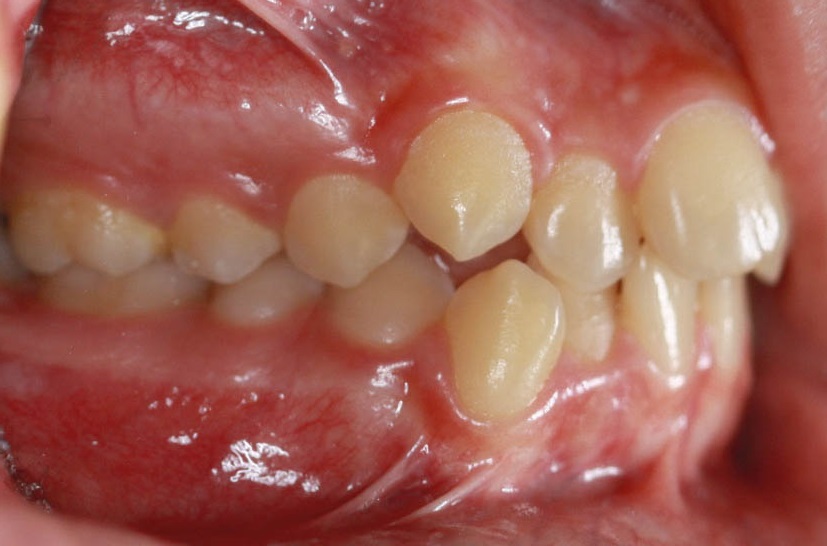

شکل 115-2: نتیجه درمان همان 2mm کلاسII تمام میشود.

وقتی 2mm کلاسII باشد (شکل 114-2) اگر پرمولرهای بالا را فقط بخاطر 2mm کلاسII بودن بکشید آن موقع برای رسیدن به یک کاسپ کامل کلاسII، مولرهای شما باید 5mm حرکت مزیالی بکنند که از لحاظ مکانیکی کاری بسیار سخت است. بیماران هم شکایتی از اورجت زیاد ندارند چون 2mm کلاسII اورجت زیادی برای آنها درست نمیکند. این بیماران را مانند بیماران کلاسI (منتهی حد مزیالی آن) قبول میکنیم و چون بنا برغیرکشیدنی بودن فک پائین است، لذا بالا را هم غیرکشیدنی درنظر میگیریم و ارتودنسی را تمام میکنیم (شکل 115-2).